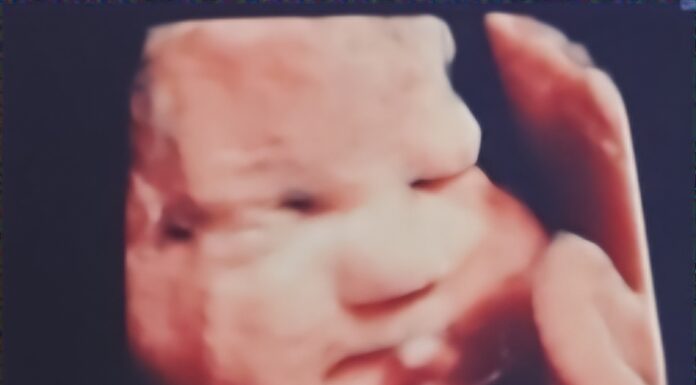

Local mother travels to Texas to seek care for unborn baby

CULLMAN, Ala. – Cullman resident Holliann Letson was enjoying a typical pregnancy with her second daughter, Evelyn. At her 18-week anatomy scan – the scan often referred to as the “gender scan,” as most babies’ genders can be determined at this stage of pregnancy...